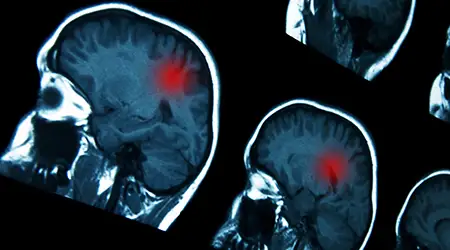

ACCIDENTE CEREBROVASCULAR (ACV) Conocido popularmente como derrame cerebral. Un ACV ocurre cuando el flujo sanguíneo a una parte del cerebro se interrumpe lo que puede ser causado por un coágulo (ACV ISQUÉMICO) o por la ruptura de un vaso sanguíneo (ACV HEMORRÁGICO). Los síntomas incluyen debilidad súbita o entumecimiento en la cara, brazo o pierna especialmente en un lado del cuerpo, confusión, dificultad para hablar o entender, problemas para ver y pérdida de equilibrio.